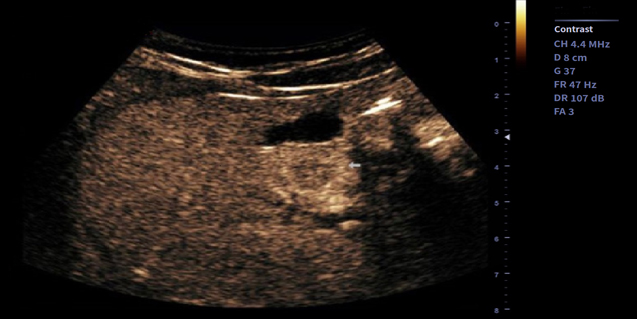

临床图像